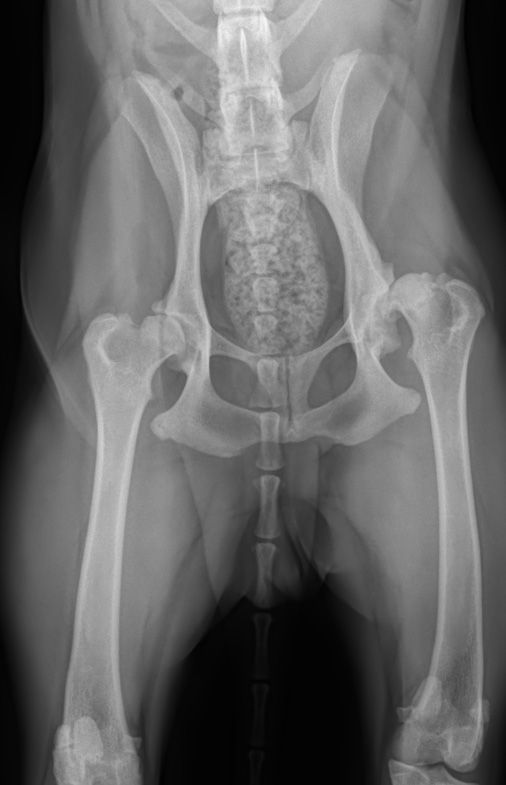

ДТБС у собак: рентгенограммы

ДТБС: степень "D" — средняя форма